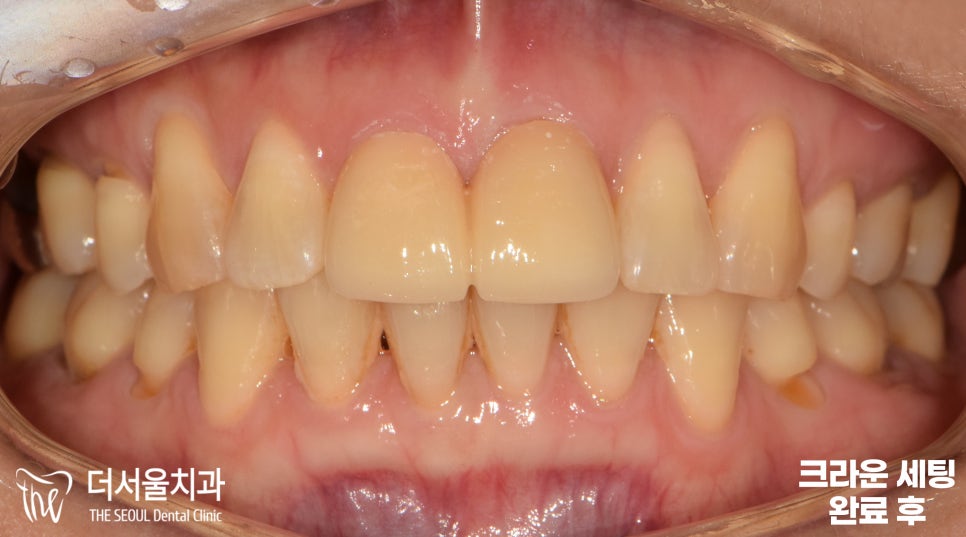

『크라운 보철 치료 결과』

깔끔하게 잘 세팅되었죠?

원래 치아와 큰 차이점이 있을까요?

색이든 모양이든 비슷하게 맞춰서

이를 구별해 내는 것이 어려우실 겁니다.

환자분 역시 이게 크라운 보철 치료한 것 맞냐며

원래 본인의 것 아니냐며

정말 놀랄 노자라며 결과에 만족해하셨습니다.